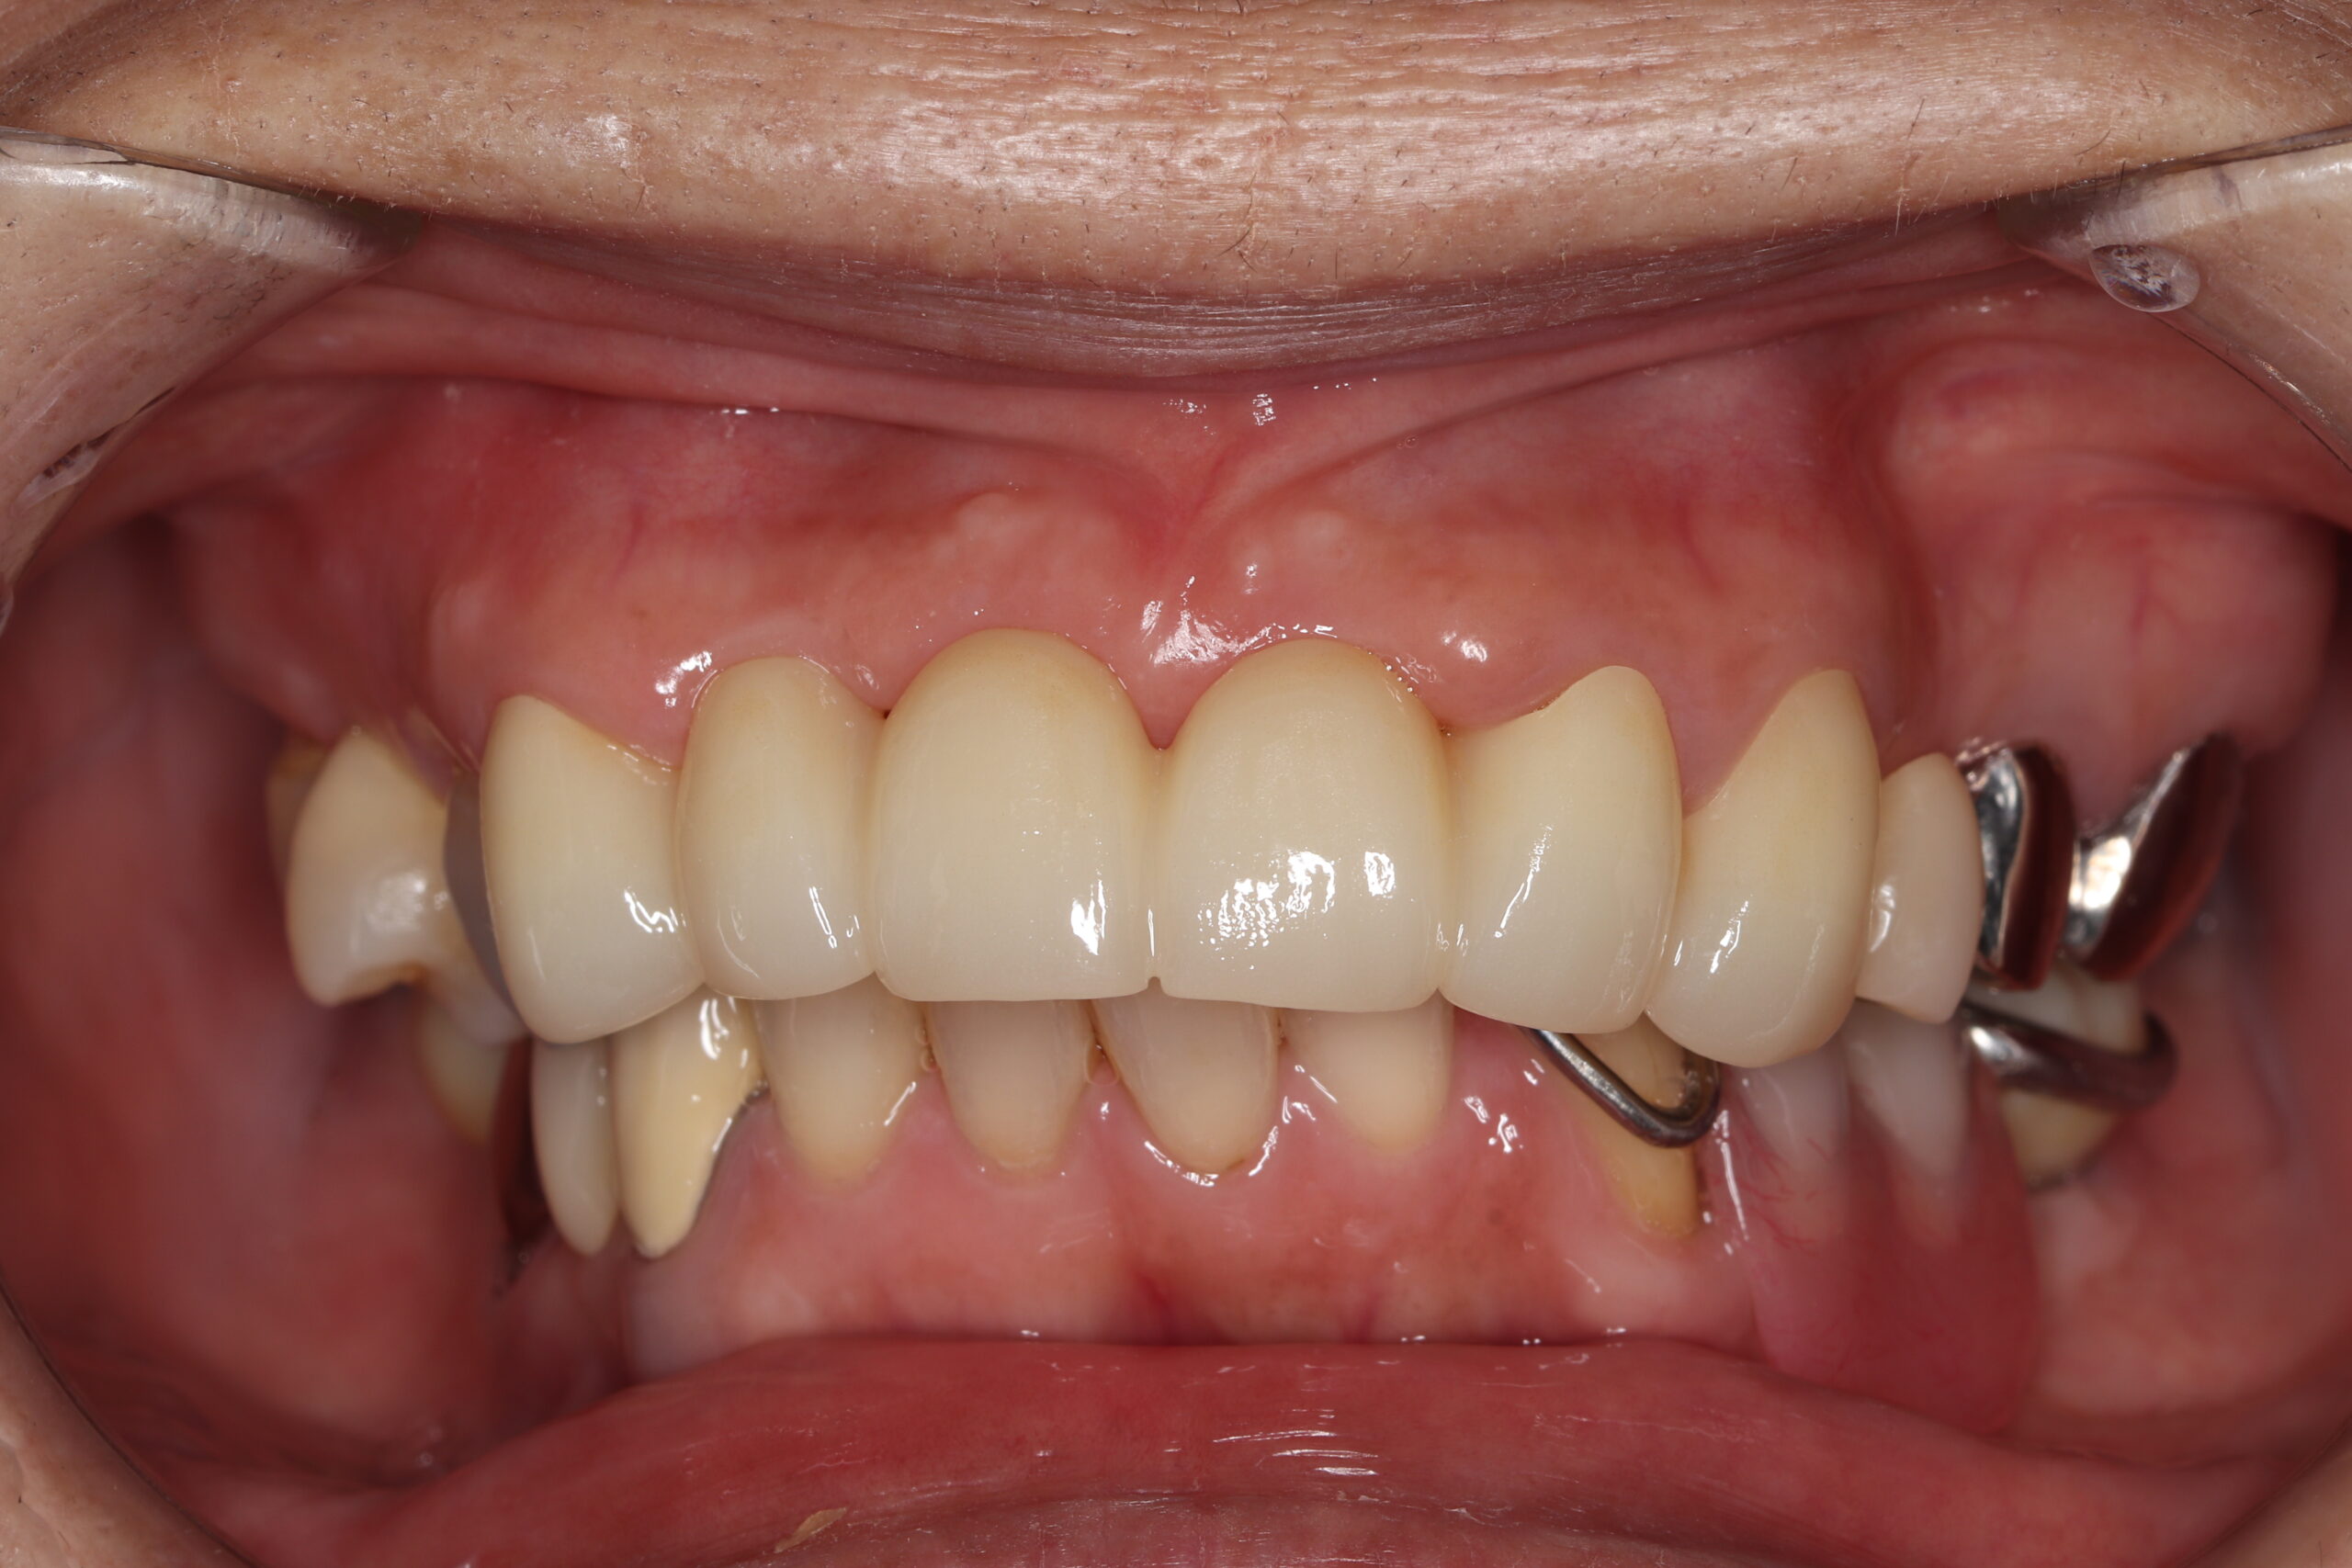

症例紹介